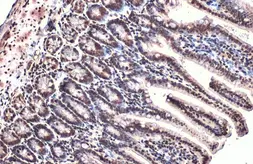

Images